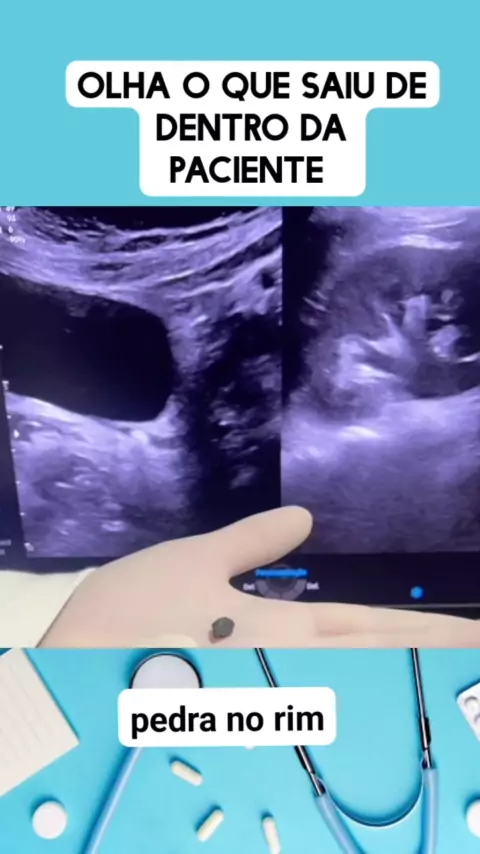

pedra no rim veja o sintoma #medico #medicina #Saúde #viraliza